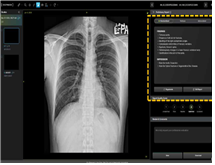

특히 주목할 만한 성과는 '생성형 AI' 기술이 적용된 의료기기의 최초 지정이다. 이번에 지정된 제품은 흉부 X-ray 영상을 분석해 42종의 질환 및 소견에 대한 판독 소견서 초안을 자동으로 생성해준다. 영상의학과 전문의는 이를 참고하여 더 빠르고 정확한 진단을 내릴 수 있게 된다.